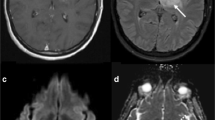

Morphologic MR imaging characteristics of RPT include contrast enhancement, mass effect, and vasogenic edema. However, similar features are also seen with TIN/radiation necrosis and/or ‘pseudo-progression’ (Fig. 1). Kumar et al. [11] characterized radiation necrosis based on morphologic imaging features and showed that (1) conversion from no enhancement to enhancement, (2) remote new enhancement, (3) new periventricular enhancement, and (4) soap-bubble or swiss-cheese enhancement will favor radiation necrosis over recurrent and/or progressing tumor. Mullins et al. [12] demonstrated corpus callosum involvement, in conjunction with multiple enhancing lesions with or without crossing of the midline and sub-ependymal spread favor predominat glioma progression thus contradicting some of the previously described morphologic features described by Kumar et al. [11]. Mullins et al. [12] also stressed that combinations of enhancement patterns were more likely than individual patterns to distinguish necrosis from tumor progression. In our experience, we have noted a high percentage of cases with histopathology proven radiation necrosis showed periventricular/sub-ependymal spread (50%) and corpus callosum involvement (27%) (Fig. 2), hence, suggesting that dependence on only morphologic imaging features could be misleading [13]. Similarly, with the increasing use of anti-angiogenic agents, the utility of only contrast enhancement as a feature of tumor recurrence has also been questioned. Non-enhancing infiltrative tumor recurrence or progression, which could occur at or away from the primary tumor site in these patients, has further unmasked the limitation of using only contrast enhancement or conventional morphologic features as the criteria for assessing treatment response [6, 9, 14, 15]. Because of the limitations of using only morphologic imaging features such as RECIST (Response Evaluation Criteria in Solid Tumors) or Macdonald criteria as a measure of treatment response, there has also been an international effort in neuro-oncology to improve imaging response assessments for high-grade gliomas by adding information about a patient’s clinical status to various morphologic imaging features, and to especially allow the interpretation of clinical trials involving anti-angiogenic agents (Response assessment in neuro-oncology working group, RANO). However, none of these criteria include any functional imaging techniques as a treatment response measure primarily because of lack of standardization of image acquisition, post-processing, and image analysis. Many of these functional imaging techniques, whether evaluating tumor physiology (DWI and perfusion imaging) or assessing tumor metabolism (MR spectroscopy, PET based imaging techniques), have been used alone or in various combinations to differentiate RPT from TIN [16–20]. We propose following a flexible algorithm in post-treatment patients, starting with conventional morphologic imaging features using standard of care follow up MR imaging and incorporating some of these functional imaging tools as needed (Fig. 3).

37-years old female with a recurrent right fronto-parietal GBM was treated with radiation therapy showed progression in the contrast enhancing lesion from (a) baseline study to (b) 6 months follow up post-radiation therapy. CT perfusion study showed reduced (c) blood volume suggesting treatment effects or radiation necrosis which was proven with histopathology

Disadvantages of MR perfusion include limited availability and more complex quantification of various perfusion parameters because of a nonlinear relationship between tissue signal intensity and contrast agent concentration as well as difficulty in assessing an arterial input function as compared to perfusion CT. Perfusion CT is more readily available and has been recently employed for assessment of brain tumors [24, 27], as well as differentiating radiation necrosis from recurrent tumors with very good success [31], and probably also has the advantage of having very robust data (Figs. 1c, 4). Use of an arterial input and a venous output function helps to generate quantitative perfusion parametric maps. Jain et al. reported a cutoff point of 1.65 for nCBV (normalized CBV) with a sensitivity of 83.3% and specificity of 100% to diagnose recurrent tumor from radiation necrosis using perfusion CT [31]. However, radiation exposure and use of an iodinated contrast agent limit the utility of perfusion CT in brain tumor assessment where as MR perfusion can be obtained as an additional sequence to standard of care contrast enhanced MRI done for these patients.

50 years old male previously treated with SRS (stereotactic radiosurgery) for cerebral metastasis from lung cancer. Post contrast T1-weighted axial images showing a recurrent heterogenously enhancing lesion in the left temporo-occipital region. Perfusion CT blood volume map showing decreased blood volume consistent with a diagnosis of radiation necrosis. Six months follow up post contrast T1-weighted axial images (extreme right) showing resolution of the enhancing lesion without any anti-neoplastic treatment